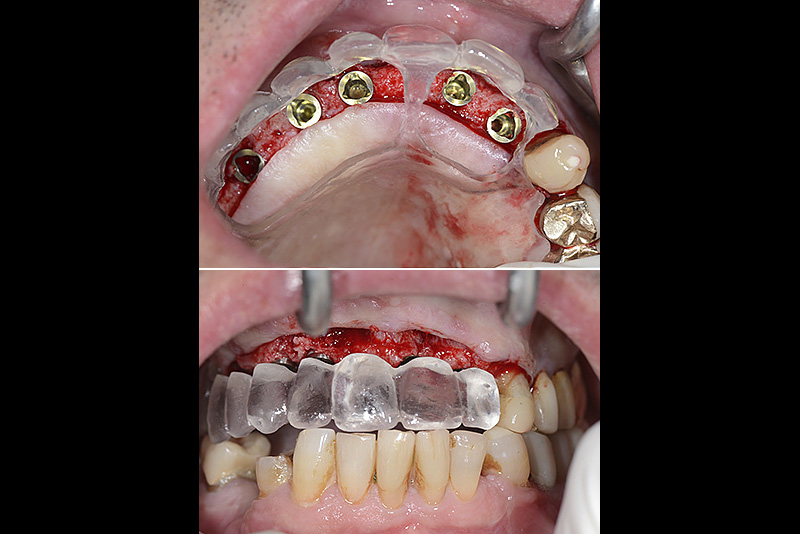

PREMESSA: in seguito all’estrazione dell’incisivo laterale superiore di destra, resasi necessaria per cause batteriche, si decide di affrontare il caso con il posizionamento di un impianto in sostituzione dell’elemento mancante dopo guarigione del sito infetto. Con tecniche rigenerative sia dei tessuti ossei mancanti a causa dell’infezione pregressa, sia dei tessuti gengivali che appaiono inizialmente troppo spostati in alto, si ripristina una corretta morfologia delle parabole (contorni) gengivali e delle papille interdentali (triangoli di gengiva tra due denti vicini).

Vengono utilizzati 2 tipi di provvisori: il primo, cementato ai denti vicini, viene utilizzato dal momento dell’estrazione del dente fino ad impianto osteointegrato (circa 6 mesi); il secondo, avvitato direttamente all’impianto, ha una funzione di prova estetica ma soprattutto di guida per la maturazione dei tessuti gengivali peri-implantari portandoli verso la maturazione completa prima di posizionare la corona finale in disilicato di litio.